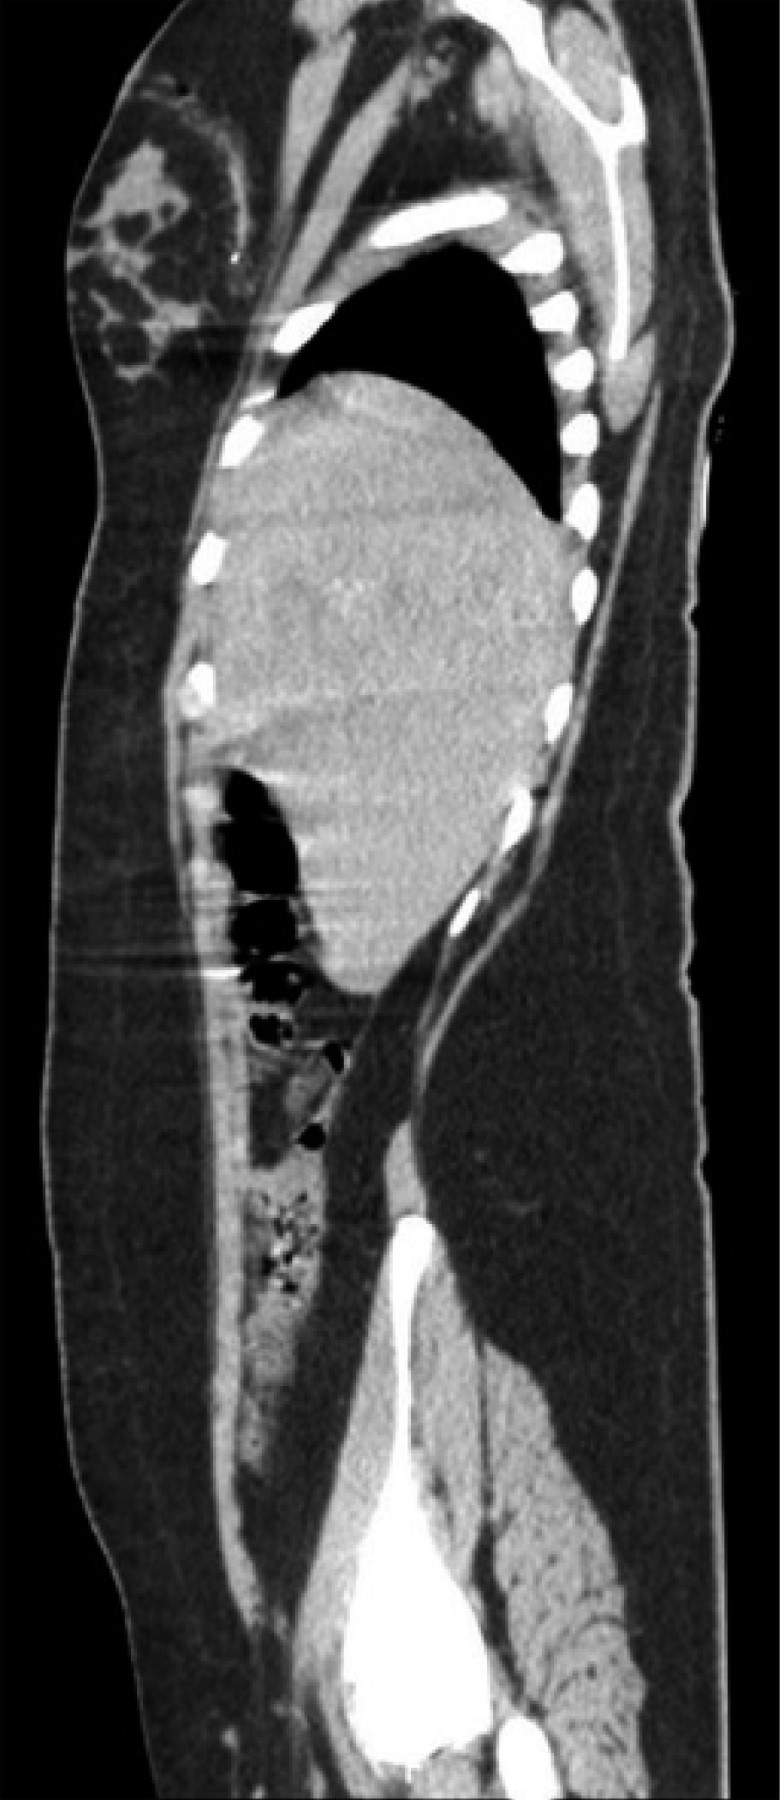

On physical examination, her vital signs were as follows: heart rate of 74 beats/minute; blood pressure of 98/67 mmHg; respiratory rate of 19/min; temperature of 36o C; and oxygen saturation of 98%. The chest showed a PAF entry orifice in the upper outer quadrant of the right breast (Figure 1), and the lung fields were well-ventilated. The abdomen was flat, with peristalsis, soft and painless to palpation. The blood cytology reported a hemoglobin of 12.8 g/dL, hematocrit of 36.4%, and white blood cells of 6,400/ml. The chest X-ray ruled out pneumothorax (Figure 2). A CT scan of the thorax and abdomen showed a metallic foreign body lodged in the right parasagittal line at the level of the 12th thoracic vertebra (Figure 3), without pulmonary or diaphragmatic lesion (Figures 4 and 5); in the abdomen, a PAF tract was observed with a 12 cm by 2.3 cm grade IV liver lesion in segments IV, VII and VIII of Couinaud (Figure 5), scarce free fluid, without lesion of any other organ (Figures 3, 5 and 6). Twenty-four hours later, a control CT scan was performed, showing the liver lesion without subcapsular collection or active extravasation on the application of contrast medium, without an increase of free fluid. Given the correlation of these findings with clinical stability, the patient was discharged on the fourth day of her admission. She did not have any complications one month after her discharge.

Figure 3

Figure 4

Figure 5

Figure 6